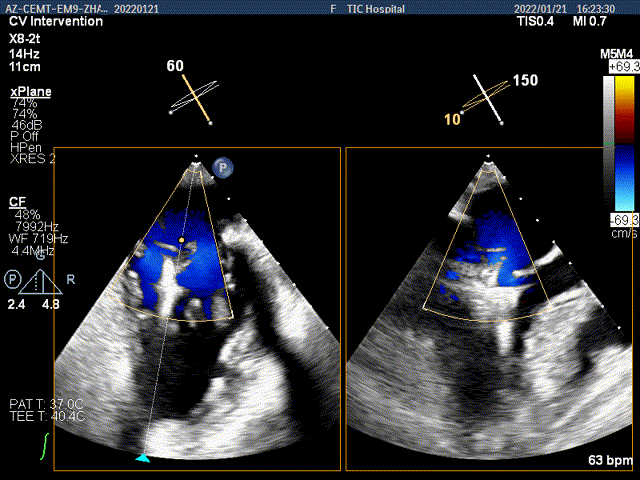

夹子放置后二尖瓣口平均跨瓣压差:1mmHg

肺静脉血流频谱恢复正向

x-plane验证前后叶抓捕后bond明显